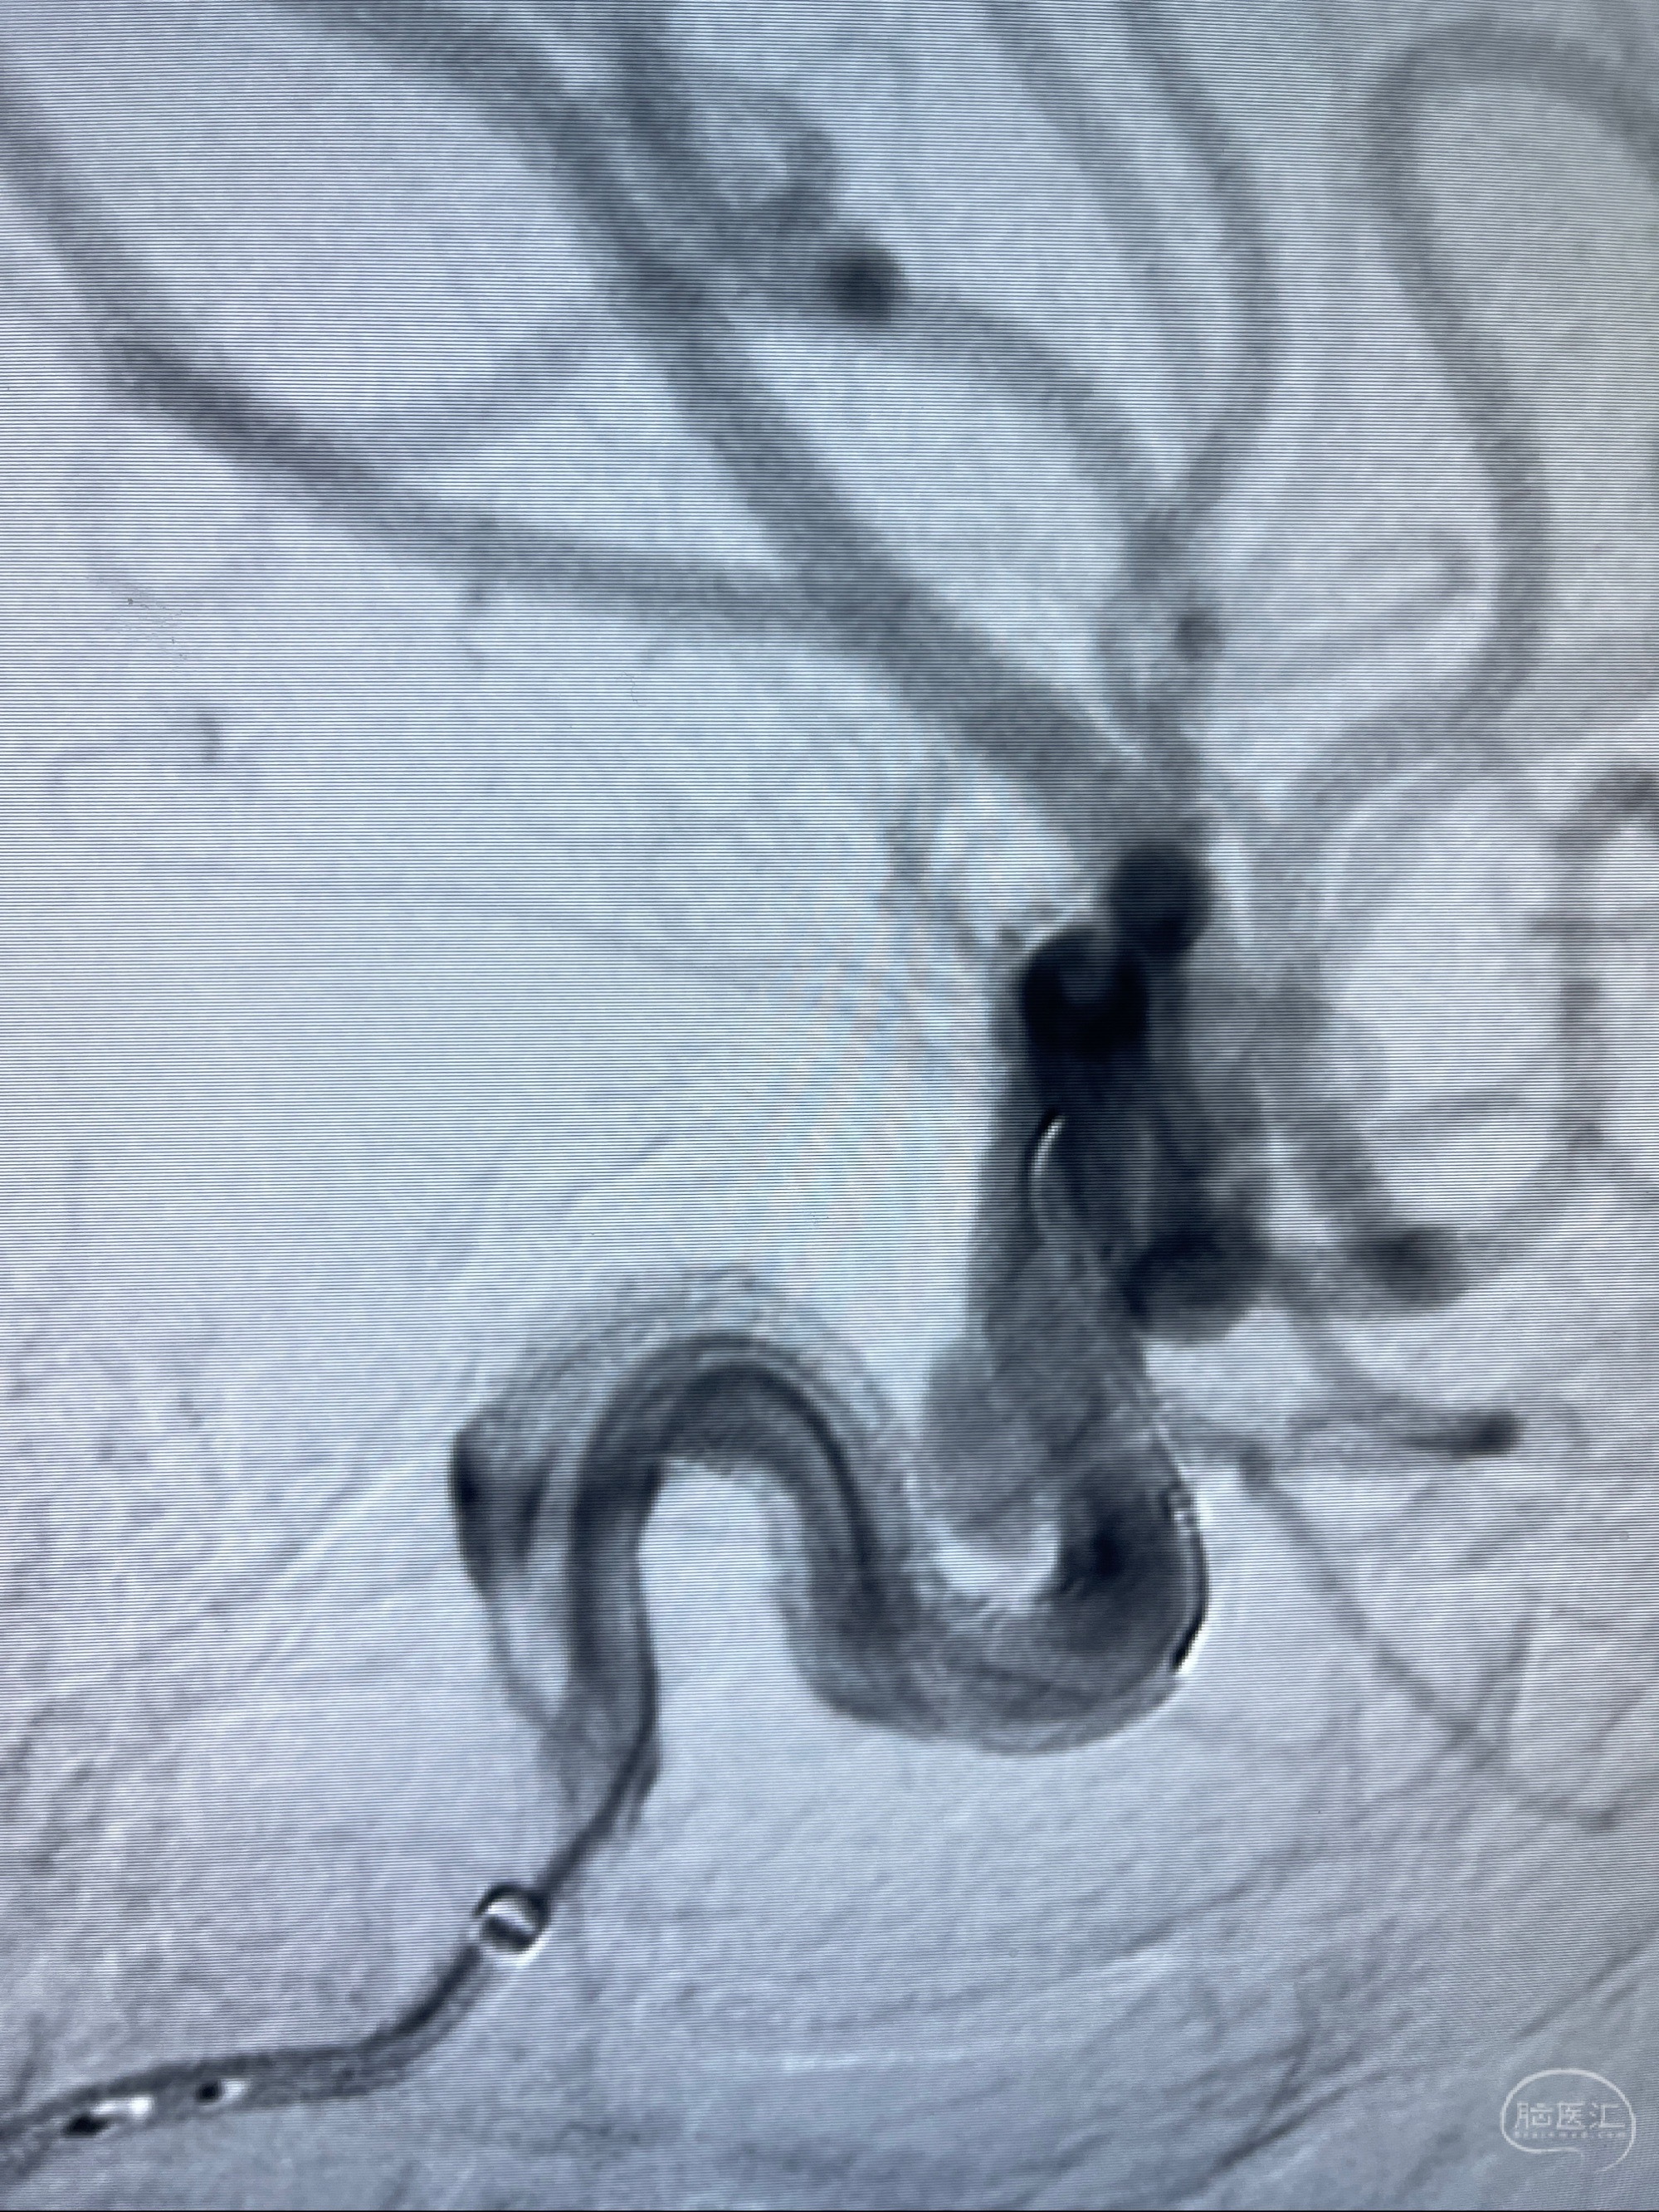

2023.07.25 泰州市人民医院查头颅CTA提示右侧C6段瘤样突起,建议DSA检查;

CTA示:右侧颈内动脉C6段见指向下方的突起,余左侧颈内动脉、双侧椎动脉、大脑前动脉、大脑中动脉、大脑后动脉及基底动脉走形正常,未见明显扩张及狭窄,局部未见明显瘤样扩张。

2023-07-27全脑血管造影:双侧颈内动脉眼动脉段动脉瘤,右侧较大

2023-08-01全麻下行双侧颈眼动脉瘤支架辅助栓塞

术后即刻CT